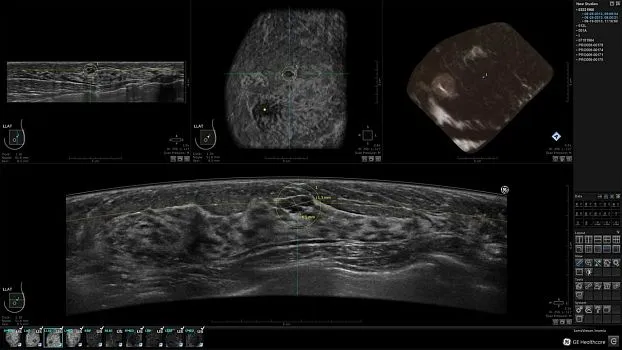

Клинические изображения

• Получение объемных 3D изображений с возможностью покадрового просмотра

• Получение изображений:

• Поперечная плоскость (в реальном времени)

• Коронарная плоскость (статическая, для указания нахождения соска)

• Отображение объемных 3D ультразвуковых изображений, которые состоят из традиционных поперечных и воссозданных коронарных и сагиттальных проекций